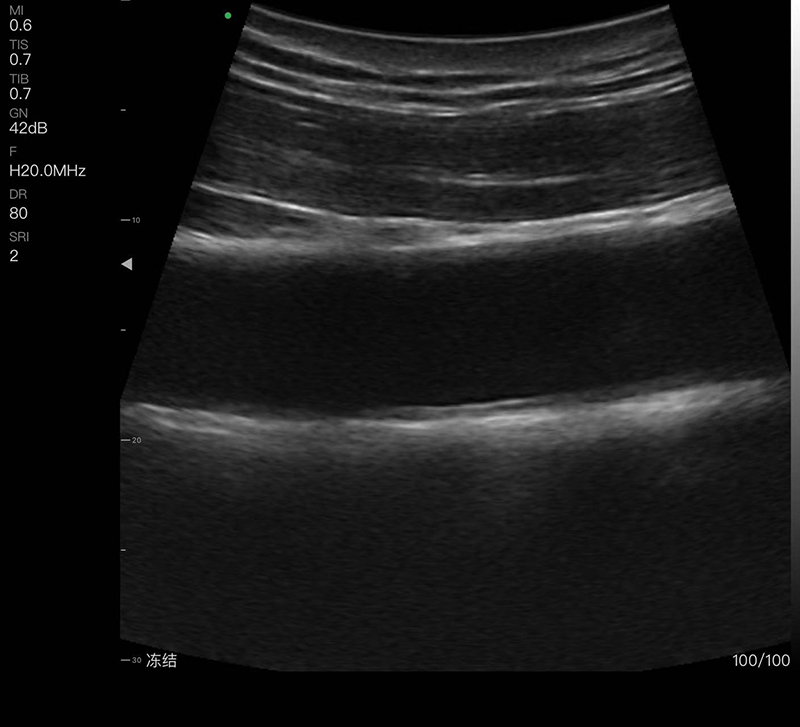

A must-have handheld ultrasound device with a fingertip probe that can be easily carried in your pocket. With a small handheld device, you can easily take pictures and images by placing the probe on your fingers, freeing your hands from the need to hold the probe and allowing you to hold other things. It is particularly suitable for surgery.

• Scanning Depth: 10/20/30/40mm, adjustable

• Display mode: B, B/M, Color, PDI, PW